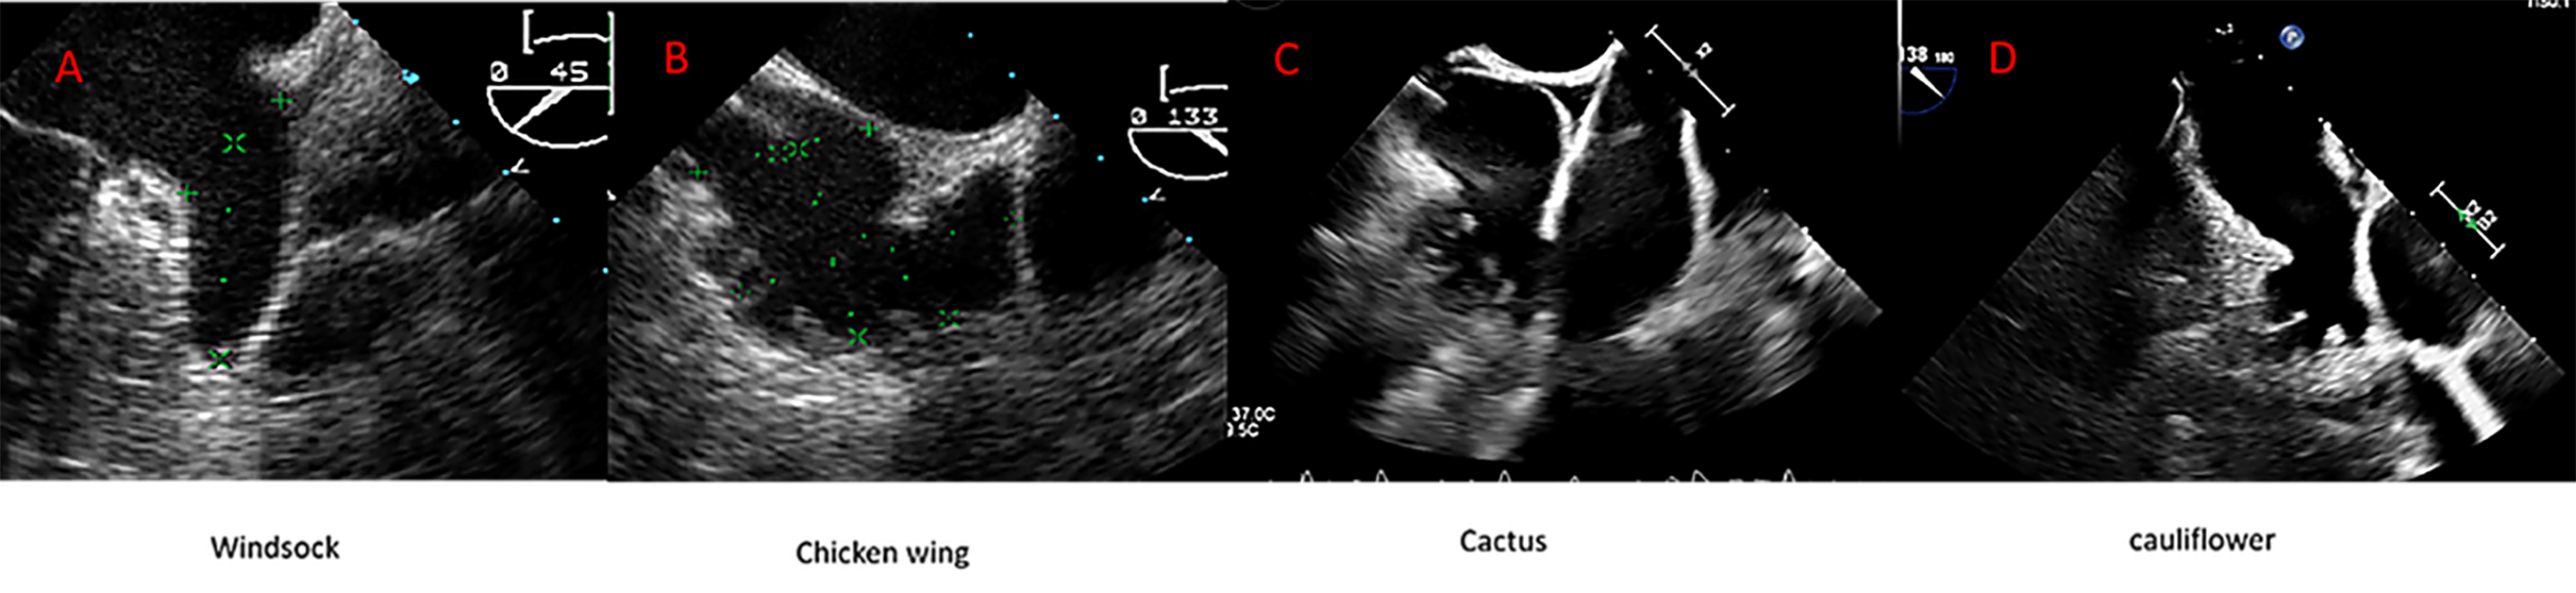

The LAA is separated from the left superior pulmonary vein (LSPV) by the Coumadin ridge, an endocardial fold that externally corresponds to the ligament of Marshall. The LAA may have one or more lobes or protrusions, which are extensions of its functional portion [17]. Based on cardiac computed tomography (CCT) findings, Wang et al. [18] classified the LAA into four main morphologies: windsock, cauliflower, cactus, and chicken wing (Fig. 2). The authors also described the spatial relationship between the LAA and the LSPV, categorizing it as high type (superior to the LSPV), a mid-type (parallel to the LSPV), or a low type (inferior to the LSPV). Among these, the chicken-wing morphology is the most common variant and is generally considered the most challenging for percutaneous closure due to its broad ostium and shallow depth. Conversely, the cauliflower morphology has been most frequently associated with embolic events [16, 19].

Fig. 2.

Anatomic variant of the left atrial appendage (LAA) depicted by transesophageal echocardiography (TEE). (A) Windsock; (B) Chicken wing; (C) Cactus; (D) Cauliflower.

Of note, the current morphological classifications have demonstrated limited predictive value for procedural complexity and clinical outcomes in LAAC [18]. Therefore, additional anatomical and functional parameters should be considered during preprocedural planning, as discussed later in this review.